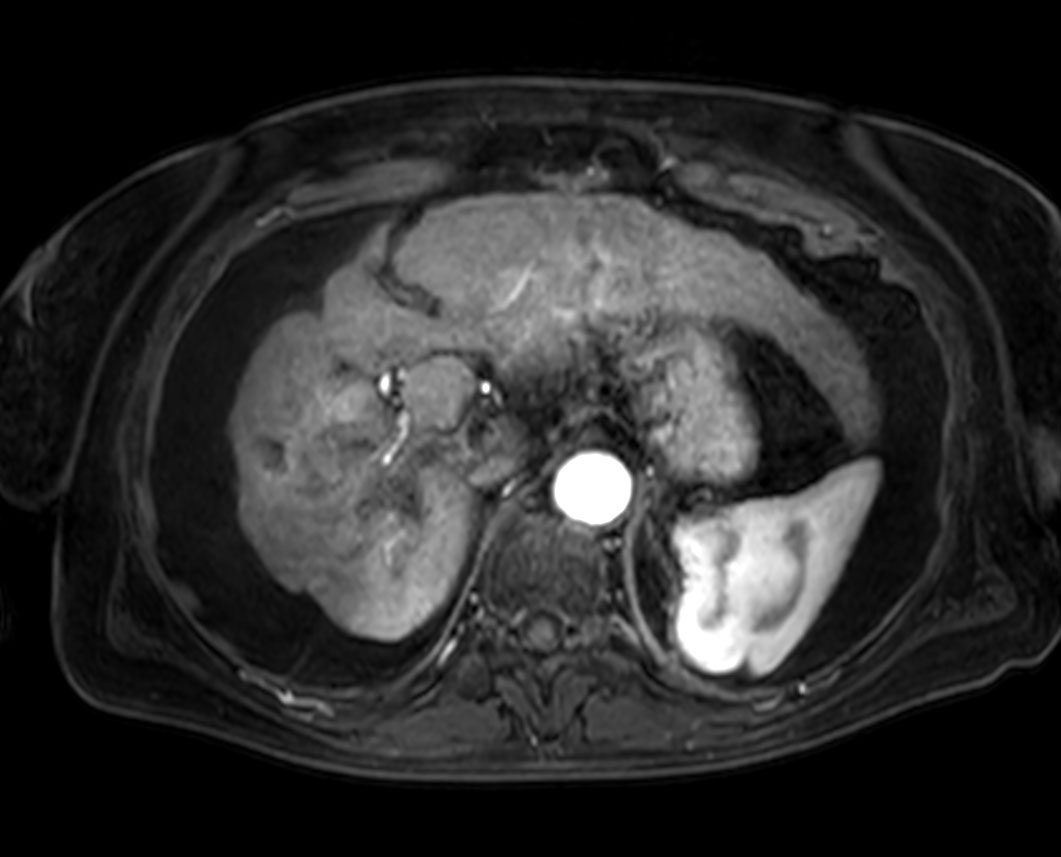

Axial T2w TSE